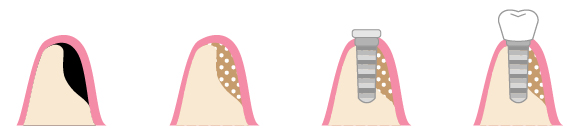

そのため、あごの骨が少ない方がインプラント治療を受けるためには、あごの骨を補填しなければなりません。ここでは、あごの骨を補填する施術についてご紹介いたします。

骨の厚みや高さが足りない症例では、以下のような骨造成術を行って対応します。 残っている骨の量や厚み、欠損している歯の位置などによって、最適な骨造成術が変わるため、精密な治療前検査が必要不可欠です。

GBR法

骨の厚みや高さを補いたい部分をメンブレンと呼ばれる人工膜で覆い、その中に骨補填剤(人工骨など)を詰めて、骨の再生を促します。骨補填剤を使用せず、自家骨(自身の他の部位の骨)を移植することも可能です。

ソケットリフト

ソケットリフトは、残っている骨の量が5mm以上ある場合に適用される骨造成術です。上顎洞と呼ばれる目の下・鼻の横の空洞部分に隙間を作り、そこに骨補填剤を注入します。サイナスリフトより簡易な骨造成術です。

サイナスリフト

サイナスリフトは、残っている骨の量が5mm以下の場合に適用される骨造成術です。歯が生えていた箇所の側面の歯ぐきを切開し、骨に穴を開け、そこに骨補填剤を詰めていきます。ソケットリフトと比べて大掛かりな手術になりますが、その分だけ再生できる骨の量も多いです。